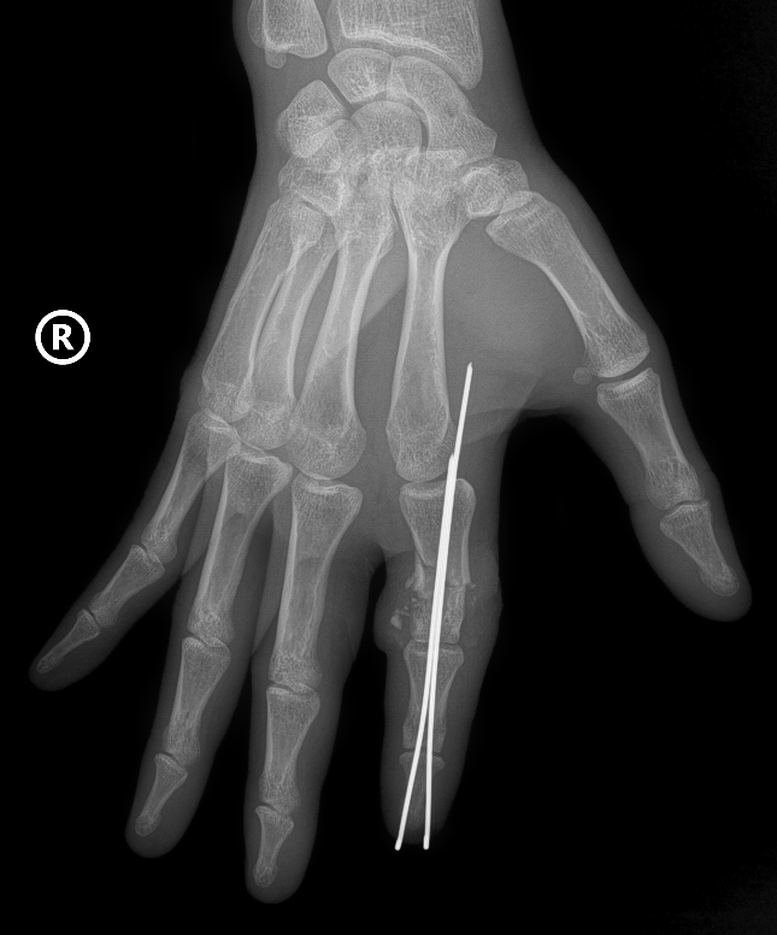

Xương ngón được định vị và cố định bằng kim chuyên dụng để tạo trục vững, hệ thống gân và dây chằng được phục hồi. Đặc biệt là thần kinh và các mạch máu nhỏ li ti chỉ khoảng 0,8 – 1mm được phục hồi với độ chính xác cao dưới kính hiển vi phẫu thuật cùng dụng cụ đặc biệt, nhằm đảm bảo phục hồi lưu thông tưới máu cho phần đứt rời.

Sau phẫu thuật, vết thương của bệnh nhân đã liền, ngón tay hồng, sống hoàn toàn, người bệnh đã có thể cắt chỉ và rút kim cố định. Hiện, bệnh nhân đang được tập phục hồi chức năng để lấy lại khả năng vận động và cảm giác của ngón tay.